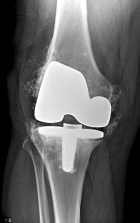

49 yo male with persistent and worsening R knee pain following TKA in 2005. He denies constitutional symptoms.

PE: RLE: mild knee effusion with tenderness to palpation at joint line. He achieves 60 degrees of flexion, lacks 5 degrees of full extension. No significant erythema. NVI w/o LAN.

Zoom image: Radiological image Radiological image.